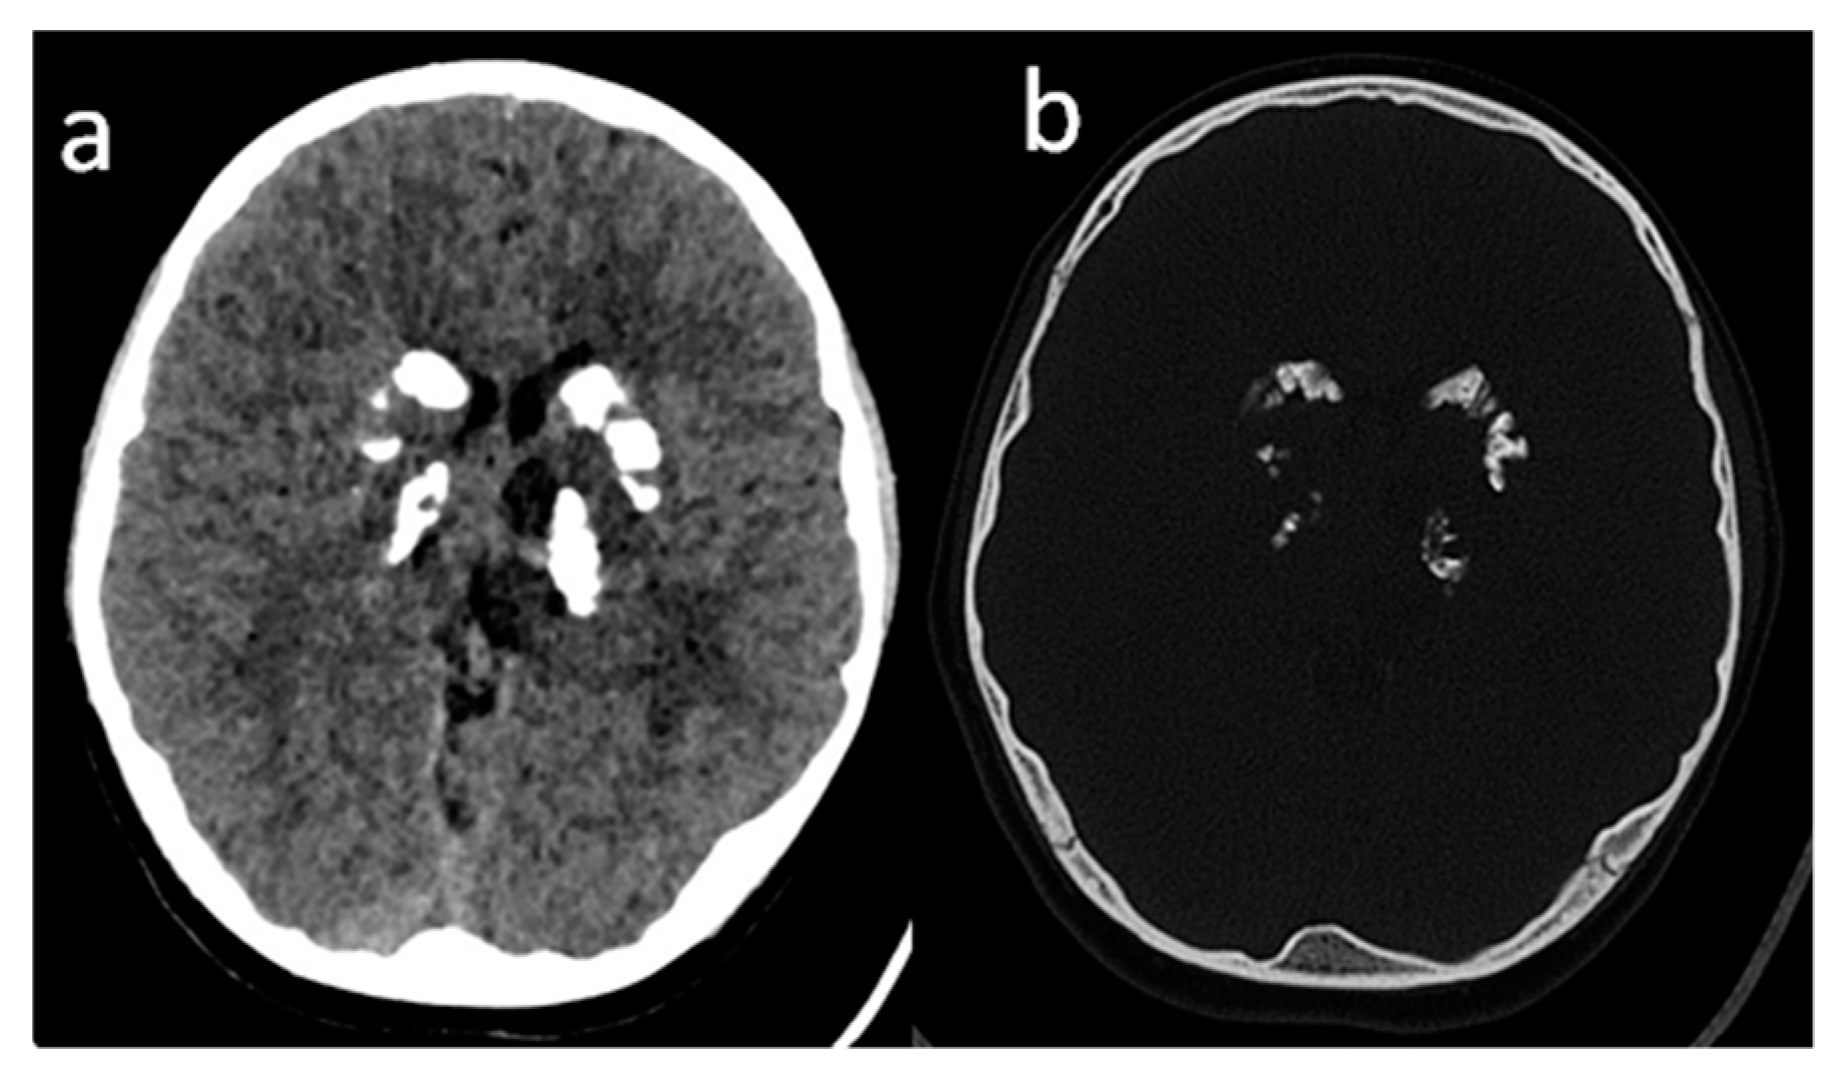

2. Case Report